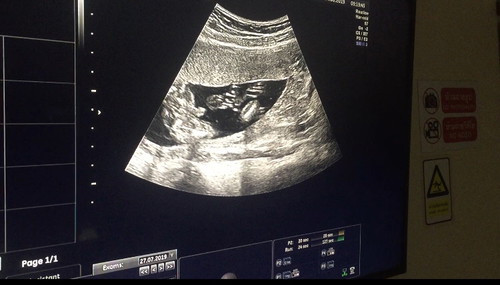

17 Weeks. อัศจรรย์

ดีใจสุดๆครับ คุณหมอบอกว่าเด็กแข็งแรงดี เห็นเพศแล้ว